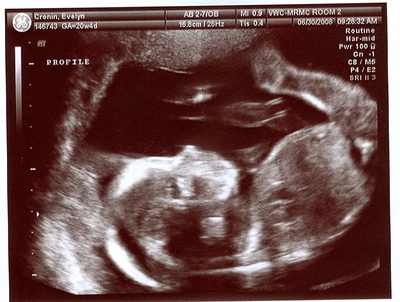

Profile Shot: